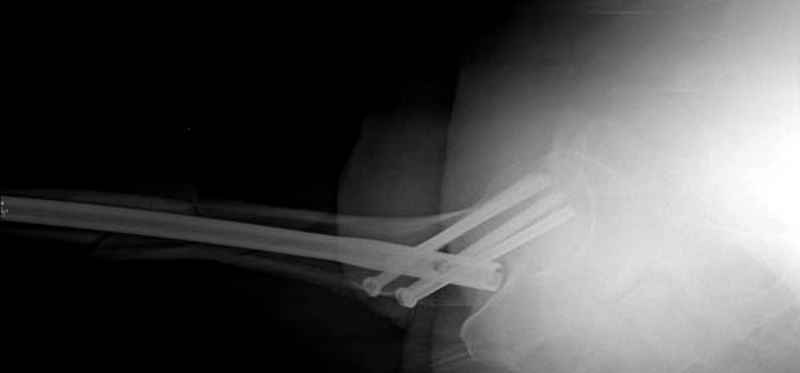

Учитывая, что случай ургентный, больной поступил вечером, не стали делать вытяжение и срочно провели операцию по фиксации перелома бедра антеградным штифтом Versa Nail от DePuy.

Для профилактики дальнейшего раскола в шейке предварительно во время проксимального рассверливания спереди и сзади провели временные спицы, которые в дальнейшем были заменены на шурупы (miss nail method)